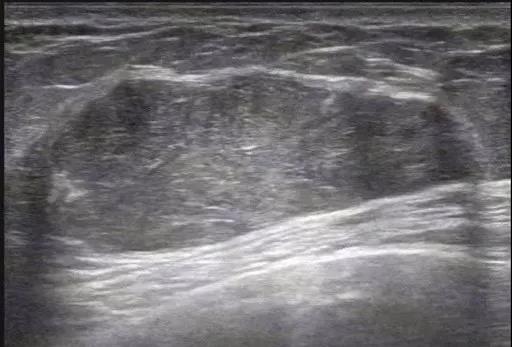

良性叶状肿瘤:肿块较小,边界清,无明显包膜,低回声,未见明显血流,比较难诊断。